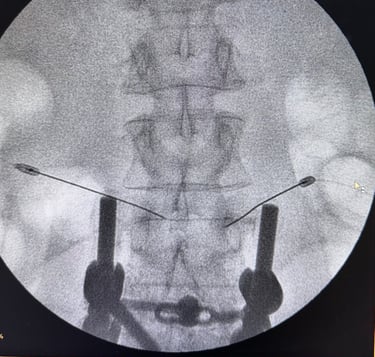

Neurocirurgia endovascular

Tratamento de doenças vasculares do cérebro e da medula espinhal por meio de técnicas minimamente invasivas — realizadas por cateteres, sem a necessidade de incisões cirúrgicas.